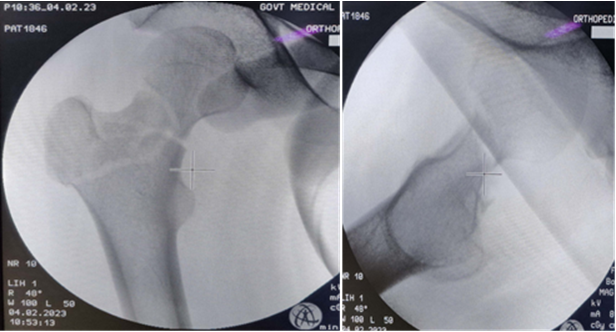

(Pre- and post-operative computed tomography was not advised as the fracture pattern was adequately distinguished in X-rays and to avoid excessive radiation exposure). The patient was posted for surgery within 48 h of trauma. With the patient on the fracture table, gentle traction was given and a satisfactory closed reduction could be achieved. After confirming reduction under C-arm, we proceeded for percutaneous partially threaded CC screw fixation (Fig. 2).

Figure 2: – C- arm images post- reduction.